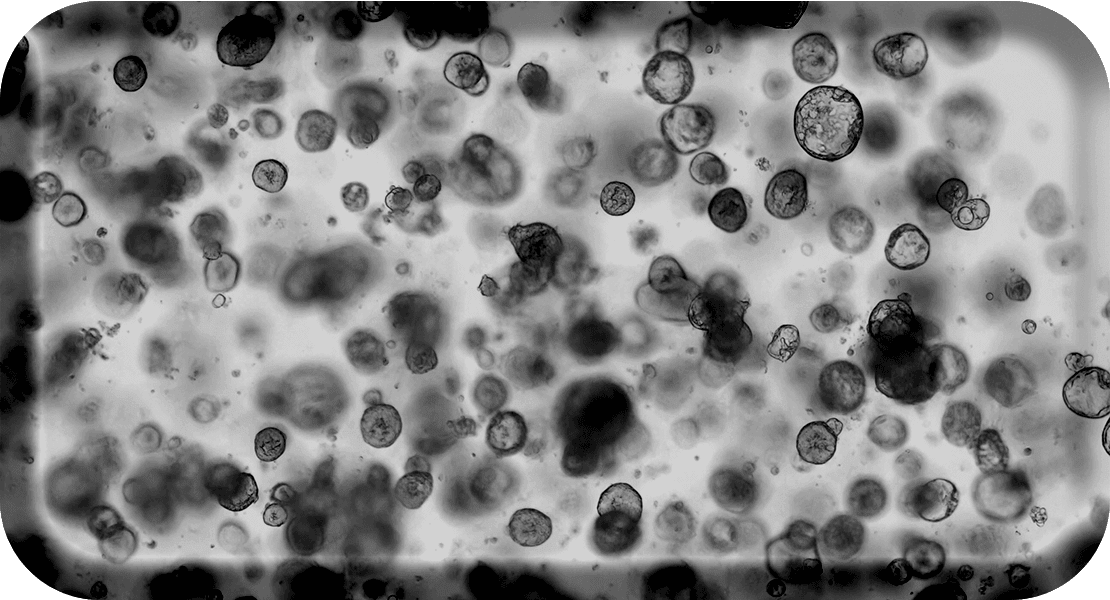

Les tumoroïdes, structures multicellulaires tridimensionnelles obtenues directement à partir d’échantillons tumoraux de patients, reproduisent de façon fidèle les caractéristiques histologiques et moléculaires de la tumeur dont ils dérivent.